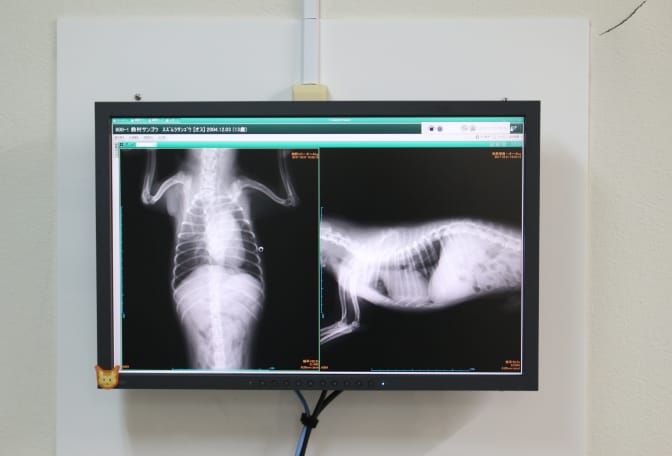

CR装置

短時間ででき、撮影されたデジタル画像は接続された診察室のディスプレーで確認可能します。飼い主様への説明もより分かりやすくなると思います。フィルムと違い劣化しないので過去の記録もすぐに呼び出せ、同じ状 態で比較できます。